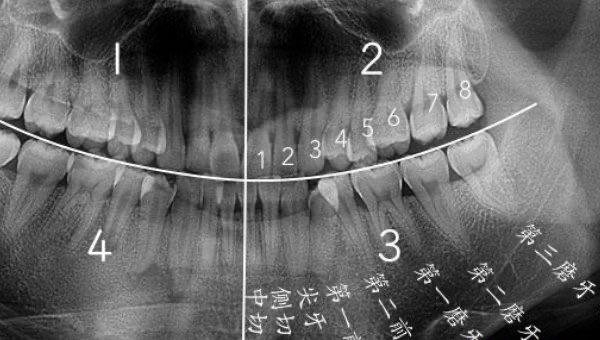

智齿是人类口腔内牙槽骨上最里面的第三颗磨牙,由于它经常会产生疼痛感,很多人选择将其拔掉,但部分人表示拔智齿后悔死了,那么这是为什么呢?快和小编去看看吧。

人在成年之后一般都会长智齿,在其生长期间可能会出现牙龈肿痛的情况,严重影响人们的日常生活,所以很多医生都建议将其拔掉,但总有人会因为拔掉后出现的不良反应而后悔。事实上,智齿对人的危害没有那么大,如果其生长状态比较良好,则没有强行拔除的必要,除非是畸形智齿。